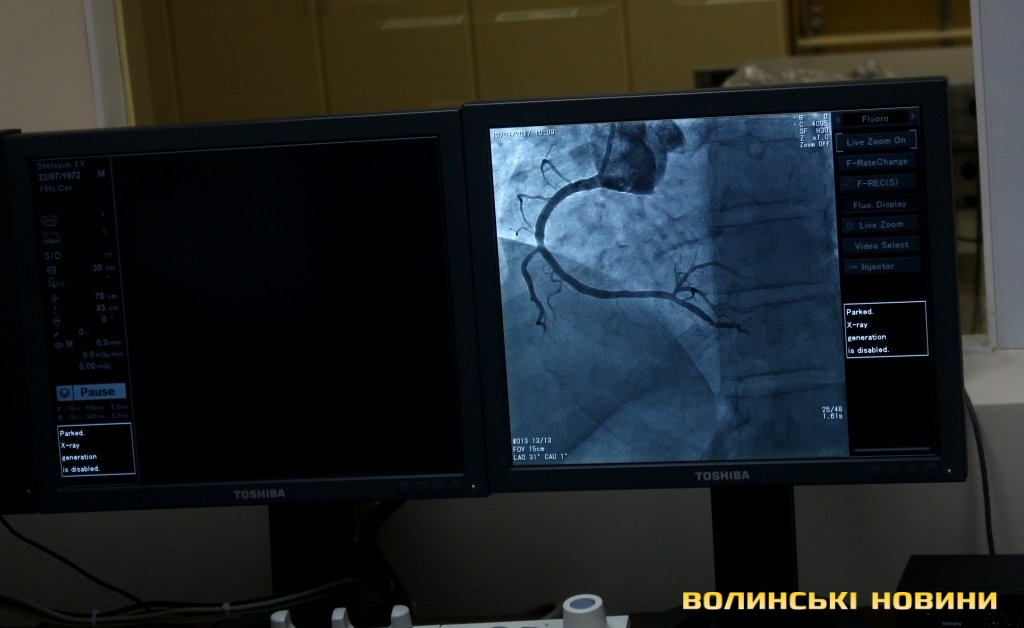

Протягом 2016 року здійснили 257 стентувань, прийняли 382 пацієнтів з інфарктом міокарда. Після стентування летальність становить лише 4,3%, після здійснення тромоболізису – 8,2%. Кількість коронарних втручань збільшилася від 103 у 2013 році до 700 у 2016 і вже 255 протягом поточного року. 70% всіх процедур здійснюють мешканцям міста. Наразі процедури фінансували з обласного бюджету в рамках програми «Волинькард», місто лише торік виділило вперше 300 тисяч гривень. До 500 тисяч гривень щороку залучали з муніципальної лікарняної каси.Лариса Духневич зауважила, що ціна стентування недешевим стентом становить до 30 тисяч гривень, а іноді пацієнту потрібно поставити одночасно 3 стенти на 3 закриті судини. Найдешевші бюджетні стенти, які купують, коштують у межах 20 тисяч. З її слів, в області 83% стентувань при гострому інфаркті міокарда роблять в міській клінічній лікарні.Роботу ангіографа продемонстрували депутатам, пояснивши, що під контролем цього апарату лікар має змогу бачити серце пацієнта під постійним рентгенівським випромінюванням, провести стент та відкрити судину. Основним агрегатом ангіографа є рентгенівська трубка, яка, як виявилося, після 4 років використання зможе працювати ще впродовж 1-6 місяців.Професор наголосив, що система лікування пацієнтів за допомогою пристрою вже налагоджена, пацієнтів привозять як з міста, так і з різних районів області, тому зараз важливо не допустити, аби ця система зруйнувалася.